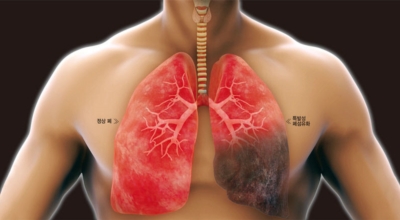

폐렴은 생각보다 무서운 병이지요. 펴렴 초기 증상 폐렴을 진단받고 현대의약으로 치료가 가능하나 폐렴 초기 증상을 방치한다면 심각한 질병으로 심각한 상황으로 갈 수 있으므로 폐렴 초기증상이 있으면 병원에서 제대로 된 검사를 받는 것이 중요해요. 오늘은 폐렴 증상에 관하여 알려드려요.

폐렴은 폐의 감염으로 인해 발생해요. 대부분의 감염은 박테리아나 바이러스에 의해 발생하지만 종종 원인을 찾을 수 없어요. 감기나 독감에 의해 유발될 수 있고, 이로 인해 세균이 폐에 접근할 수 있어요. 세균성 폐렴은 폐렴구균 박테리아에 의해 발생할 수 있어요. 이것은 가장 심각하고 잠재적으로 생명을 위협하는 유형의 폐렴 중 한가지이예요.

초기에 가벼운 기침으로 시작해 호흡하는 것조차 힘들어지게 되는데요 폐에 발생한 염증으로 인해서 폐의 신전성이 감소하고, 폐를 구성하는 폐포 세포가 망가져 적정 수준의 산소를 보관하지 못하기 때문에 호흡곤란이 유발될 수 있어요.